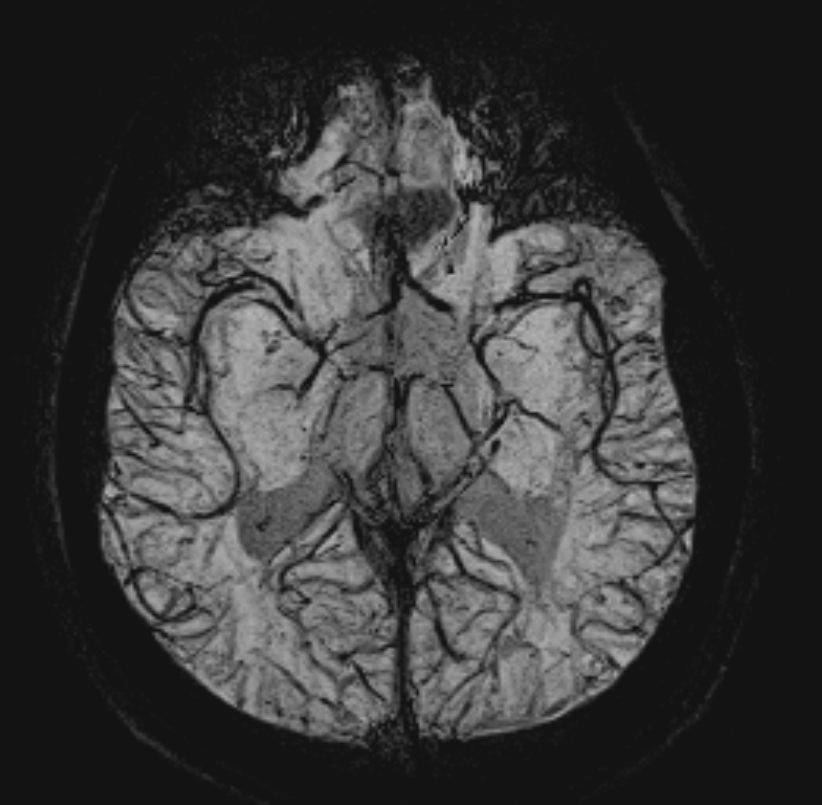

颅脑-SWI Phase MinIP

颅脑-SWI Magnitude MinIP